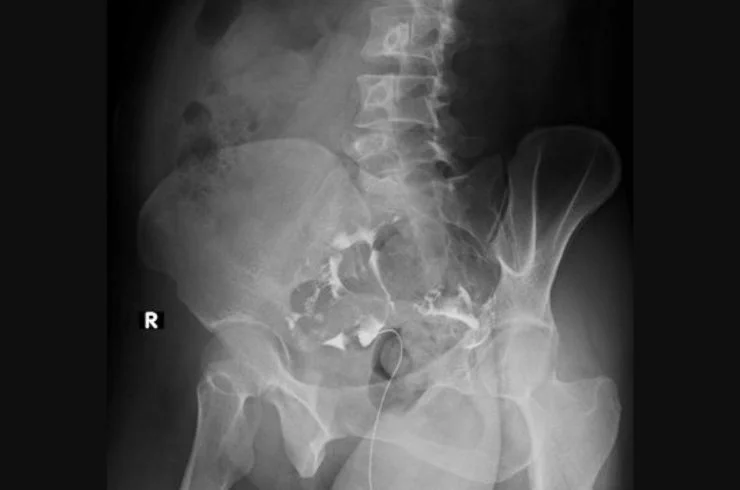

State-of-the-art X-ray technology providing clear images for diagnosing fractures, infections, and other medical conditions quickly and safely.